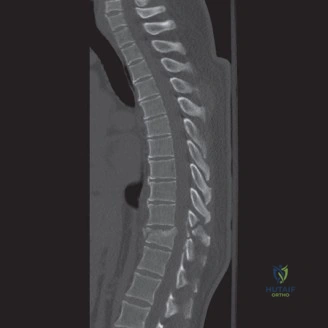

Pre-Operative Planning, Templating, and Patient Positioning

When surgical intervention becomes unavoidable, meticulous pre-operative planning is the cornerstone of a successful outcome. Advanced imaging is non-negotiable. An MRI with and without gadolinium contrast is the gold standard for defining the extent of the epidural abscess, the degree of neural compression, and the involvement of adjacent paraspinal musculature (e.g., psoas abscess). T1-weighted images typically show hypointense signals in the infected marrow, while T2-weighted and STIR sequences reveal hyperintense fluid and edema in the disc space and vertebral bodies. Gadolinium enhancement highlights the vascularized inflammatory phlegmon and the capsule of any abscesses.

In addition to MRI, a fine-cut computed tomography (CT) scan is essential for evaluating bony destruction. CT allows the surgeon to assess bone stock for pedicle screw purchase and to template the size of the interbody cages required for anterior column reconstruction. Upright standing radiographs (if the patient can tolerate them) or full-length supine films are necessary to evaluate global spinal alignment and regional kyphosis.